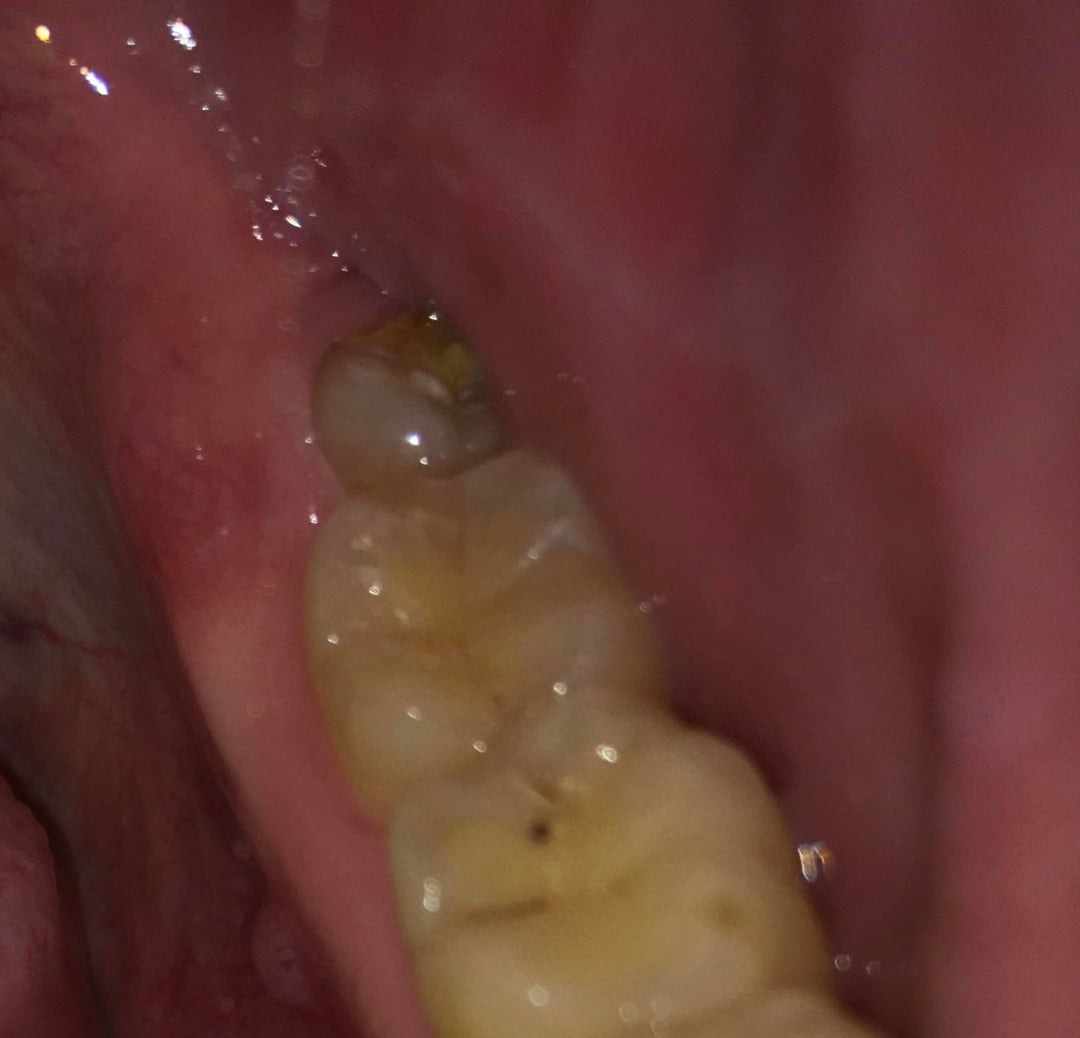

Heb al circa een week last van pericoronitis (wel vaker gehad). Deze keer duurt de genezing wat langer. Pijn is helemaal weg, maar het tandvlees daar is nog zacht en niet strak tegen de verstandskies. Foto 1 is hoe het nu is, zacht tandvlees, en foto 2 toen het gezond was waarbij het tandvlees strak is. Wanneer zal de zachtheid weggaan? Ik spoel al dagelijks met zoutwater. Ben ook van plan om in 2026 mijn verstandskiezen te verwijderen. Foto 3 en 4 zijn foto's van mijn verstandskiezen, heb alle 4 al meer dan 12 jaar niet laten trekken, maar denk dat ik het beter kan doen? Werd wel vaak gezegd tegen me dat het slim is om ze te laten trekken, maar ik ben altijd bang van zulke behandelingen.

Ik had in april dit jaar al een vraag gesteld in dit forum over mijn mogelijke erosie, u gaf toen aan dat er enige slijtage was. Ik heb totaal geen idee hoe het kan zijn ontstaan, omdat ik mijn hele leven al zowat geen suikers of prik of zure dranken nuttig. Mijn tandartsen en mondhygienisten hebben er ook NOOIT wat over gezegd. Hierbij een foto van 2015 en 2025 onderkaak tanden. Ik zie in die 10 jaar geen verschil. Is het echt flinke slijtage of valt het mee? Wat betreft mijn botniveau, heb ik inderdaad te horen gekregen dat er sprake is van lichte botafbraak, ik gebruik nu elke dag ragers. Heb in het verleden ook een beugel gehad, zou dat ook voor veranderingen in het bot kunnen zorgen? x-fotos van mijn rechter kaak uit 2010 en eind 2024.

Ik had niet begrepen dat de foto's v uw tandvlees v April waren.. De tweede foto v uw verstandkies is de reden waarom ik de opmerking heb gemaakt.